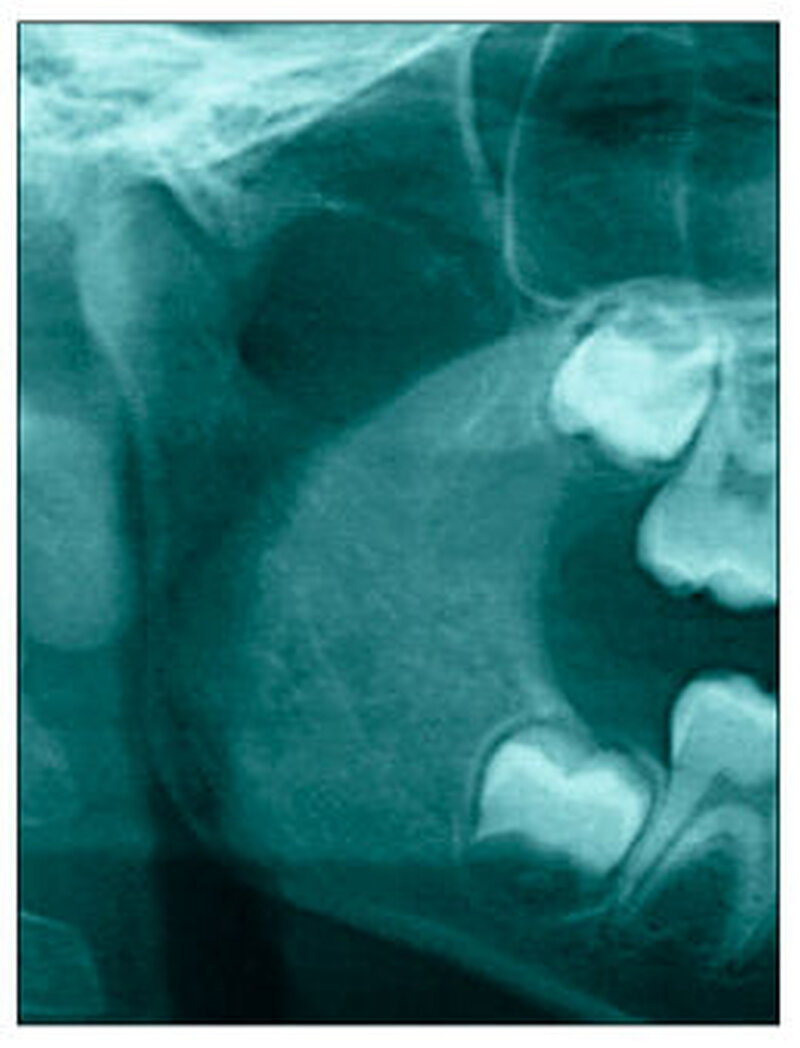

Bereits 2004 wies Carla Evans [Evans, 2005] auf das Risikomanagement bei Allgemeinerkrankungen hin und stellte am Beispiel der JIA dar, dass Unterkieferrücklagen und frontal offene Bisse aus der Kiefergelenkzerstörung entstehen können. Die Röntgenaufnahmen einer JIA-Patientin mit oligoartikulärer Form und Beteiligung des rechten Kiefergelenkes zeigen den typischen Verlauf sehr gut. Bei ursprünglich sehr dezenten Befunden, wie einer s-förmigen Mundöffnung von 44 mm, einer geringen Mittenabweichung um 2 mm nach rechts und einem frontal offenem Biss klagte sie über Schmerzen beim Essen, was den Anlass zur weiteren Diagnostik bot. Die erste Panoramaröntgenschichtaufnahme (Abbildung 1a-c) zeigt auf der rechten Seite einen abgeflachten Kondylus und eine bereits verstrichene Fossa condylaris. Ein Jahr später vermittelt das Fernröntgenseitenbild (Abbildung 1d) trotz fortschreitender kondylärer Resorption ein harmonisches Bild, während nach drei Jahren bei voranschreitendem Abbau des rechten Kondylus (Abbildung 1e) eine Rücklage der Mandibula und eine Bissöffnung manifest sind (Abbildung 1f).

Bei 152 durchschnittlich 12-jährigen Rheumapatienten wurden die kondyläre Morphologie und Symmetrie beziehungsweise Asymmetrie im Vergleich zu einer Kontrollgruppe anhand der OPG analysiert. Zur Analyse erfolgte die Zuordnung zu vier morphologischen Graden je Kondylus (Abbildung 3a-d). Bei 45 Prozent der Rheumapatienten waren morphologische Veränderungen im Rahmen kondylärer Resorption unterschiedlicher Ausprägung zu finden. Die „Kontrollpatienten“ ohne JIA zeigten nur zu 14 Prozent formatypische Kondylen. Der Unterschied zwischen den beiden Gruppen war signifikant. Daher sollte bei der Routineauswertung von Panoramaröntgenschichtaufnahmen auf diese Anzeichen geachtet werden, insbesondere auch unter dem Aspekt, dass laut Assaf [2011] durchschnittlich 4,3 Jahre zwischen Erstmanifestation der JIA und Erstvorstellung in der Rheumasprechstunde des UKE liegen.

Das Magnetresonanztomogramm (MRT) mit Kontrastmittel ist Goldstandard zum Ausschluss beziehungsweise Nachweis einer akuten Entzündung und indiziert zur Koordination therapeutischer Interventionen [Kellenberger et al., 2015]. Eine Aufschlüsselung der MRT-Befunde von 20 JIA-Patienten der Hamburger JIA-Sprechstunde aus der Dissertation von Assaf [2011] zeigt in 57,5 Prozent eine Deformierung oder Abflachung des Kieferköpfchens, bei 47,5 Prozent eine Synovitis oder Kapsulitis und bei 25 Prozent Erosionen/ Irregularitäten der Kieferköpfchenoberfläche. Diskusdeformierungen traten ebenso bei 25 Prozent auf, Gelenkspaltergüsse hatten 12,5 Prozent, eine subchondrale Perfusionssteigerung 7,5 Prozent und 5 Prozent ein deformiertes oder destruiertes Tuberculum articulare.